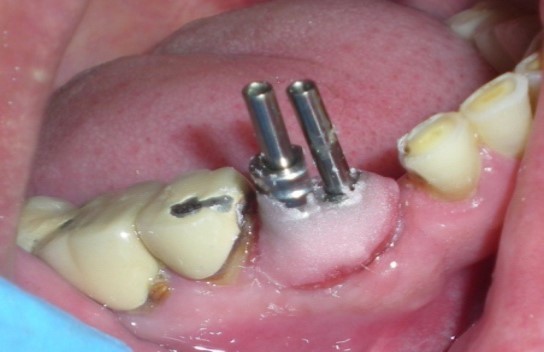

Healing abutments were cleaned and removed from mouth (Figure 2) and placed in a disinfecting solution. Direct impression coping (AlphaBio, Israel) was on one of the implants (SPI, AlphaBio, Israel) and secure it with long connecting screw (Figure 3).

Figure 2.Modified healing abutment in position.

Modified healing abutment in position.

Figure 3.Modified impression copings in proper position.

Modified impression copings in proper position.

The other impression coping was modified by holding it with artery forcep and cut it with carborundum disc so that it fits properly over the other implant. After modification, it was secured with long connecting/fastening screw to the respective implant. the complete seating of the impression copings was verified with a periapical radiograph.